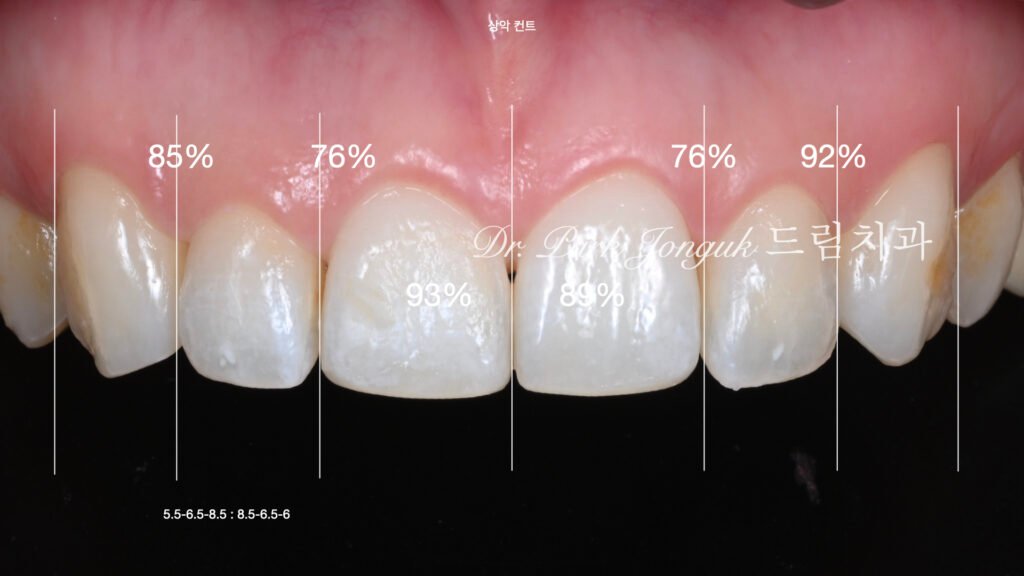

사진 2~5. 왁스업(Wax-up) 정밀진단

교정 후 악궁이 납작해진 형태를 보정하기 위해 치아 비율과 곡선을 재설계.

얼굴형, 미소선, 치아 크기를 분석하여 이상적인 조화를 계획.

사진 6. 최소삭제 과정

현미경을 이용해 0.2~0.3mm 정도의 미세한 삭제만 시행.

치아의 크기를 키우지 않으면서도 자연스러운 형태와 입체감을 표현하기 위한 과정.